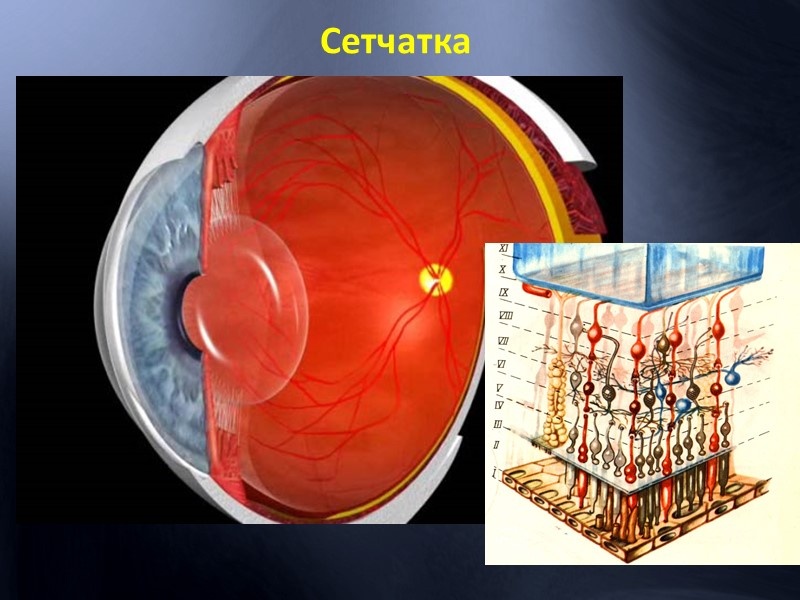

Изображения и анатомия сетчатки глаза

Раздел: Визуальный дайджест